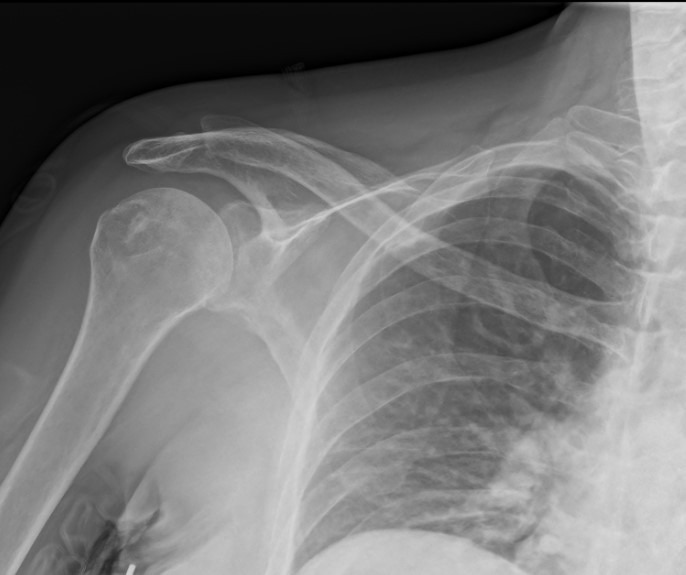

Röntgenaufnahmen sind die erste Untersuchung, bevor ein Behandlungsplan erstellt wird.

Anschließend werden Kontroll-Röntgenaufnahmen gemacht, um zu überprüfen, ob die Schulter wieder korrekt in der Gelenkpfanne sitzt, wie in der Abbildung unten gezeigt.

Die Schulter ist wieder im Gelenk.